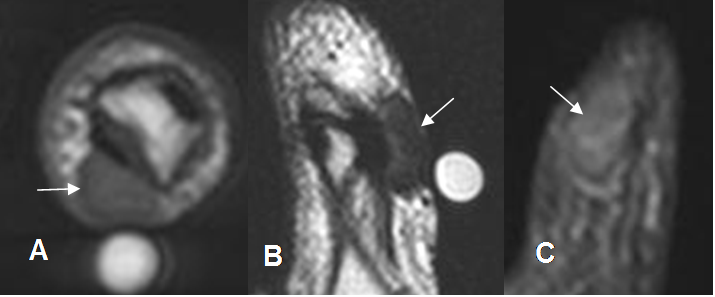

Fig 124 A. Tumor de células gigantes.

A: RM axial en T1, B: RM sagital en T2 y C: RM coronal en STIR. Tumor de células gigantes en la vaina tendinosa flexora del pulgar, manifestado por imagen ovalada y sólida, hipointensa en todas las secuencias.

Fig 124 B. Tumor de células gigantes.

A: Rx AP. Erosión de bordes escleróticos, en las bases del 4º y 5º metacarpiano y el hueso ganchoso. B: RM axial en T1 y C: RM sagital en T2. Masa de tejidos blandos hipointensa en ambas secuencias, que erosiona el hueso, por tumor de células gigantes.